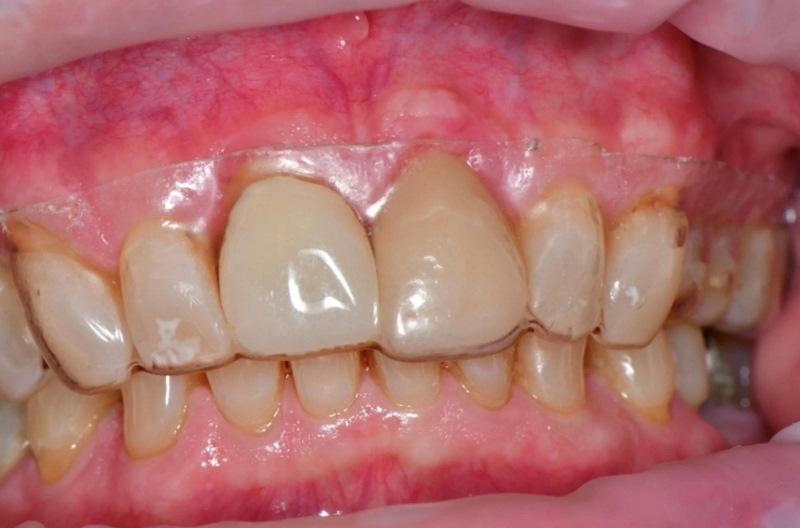

Пациент, мужчина 78 лет, обратился на консультацию по поводу перелома правого верхнего центрального резца (зуб 1.1) (Фото 1). Он пользовался временным частичным протезом для замещения коронки зуба. Пациент выразил желание заменить зуб имплантатом. При изучении анамнеза значимых соматических заболеваний не выявлено.

Фото 1. Пациент обратился с переломом правого верхнего центрального резца (зуб 1.1) на уровне десны.